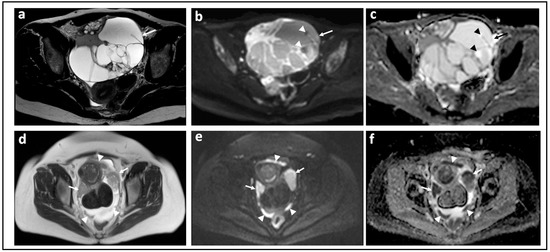

Figure 3.

Assessing disease extent using CT versus MRI: CT scan (a) T2-W image (b) and corresponding b = 1050 s/mm2 DW-MRI (c) and ADC map (d) through the mid-pelvis in a patient with high grade serous ovarian cancer before treatment. The peritoneal (arrow) and omental disease (arrowhead) is evident in (a), but the extent of peritoneal and serosal disease encasing the sigmoid colon is more striking on MRI (open arrows) where it appears as high signal within the pelvis in (c). Marked diffusion restriction is confirmed in (d).